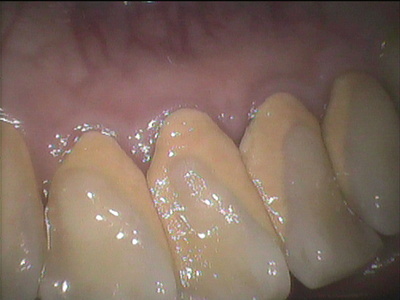

そもそもなぜ歯石って出来るんでしょうか?

いきなり硬いものが歯に飛んできてバシンとくっつくのでしょうか?

いえいえ、そんなはずありませんよね

「シセキ」って歯の石と書きます。

とても硬いんです。

指で触られた方もいらっしゃるかもしれません。

硬くこびりついているから、歯ブラシでは除けられない硬さになったということです。

最初からそんなに硬いのか?そんな訳ないですね。

段々と硬くなっていくのです。

では歯ブラシで除けられない硬さになるってどれくらいの期間がかかるのでしょう?

報告ではいろいろありますが、だいたい1週間と言われています。

1週間も汚れがずっと溜まり続け蓄積していった結果、それが歯ブラシでは除けられないくらいの硬さ、歯石となり歯ブラシでは除けられなくなり、歯科医院でガリガリガリガリ、もしくは超音波の歯石除去、スケーラーという器具でもってガリガリガリガリと除けなければ除けられない状況になってしまった、ということですよね。